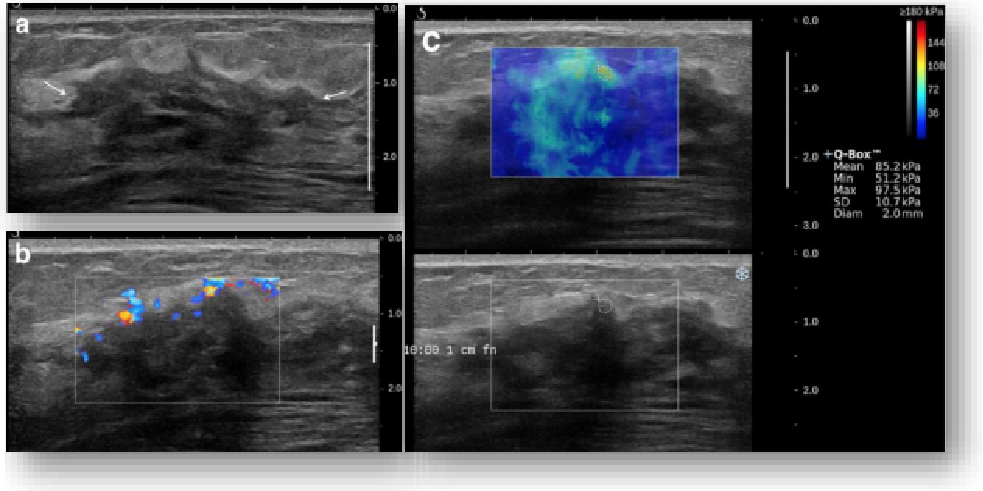

实时剪切波弹性成像

评估组织的软硬,并且提供定量数值,从而提示组织的良恶性。

鉴别诊断、精准分级、定量评价、穿刺引导、疗效评估、随访观察

恶性占位常常向周边组织进行侵润及扩散,二维很难观察到浸润部分的边界。使用实时剪切波成像能够对占位及周边组织进行硬度评估,通过颜色编码来区分不同组织的硬度信息,直观的观察占位组织的边界信息,更方便区分占位组织和正常组织的边界,准确评估消融范围。

左图病例所示:

钼靶阴性,B型发现非肿块病变

剪切波弹性成像见明确的硬度增高区域。

穿刺及手术病理结果:浸润性导管癌(IDC)

非肿块型病变:B型图像无法确认病变范围,E成像帮助发现异常区域和评估